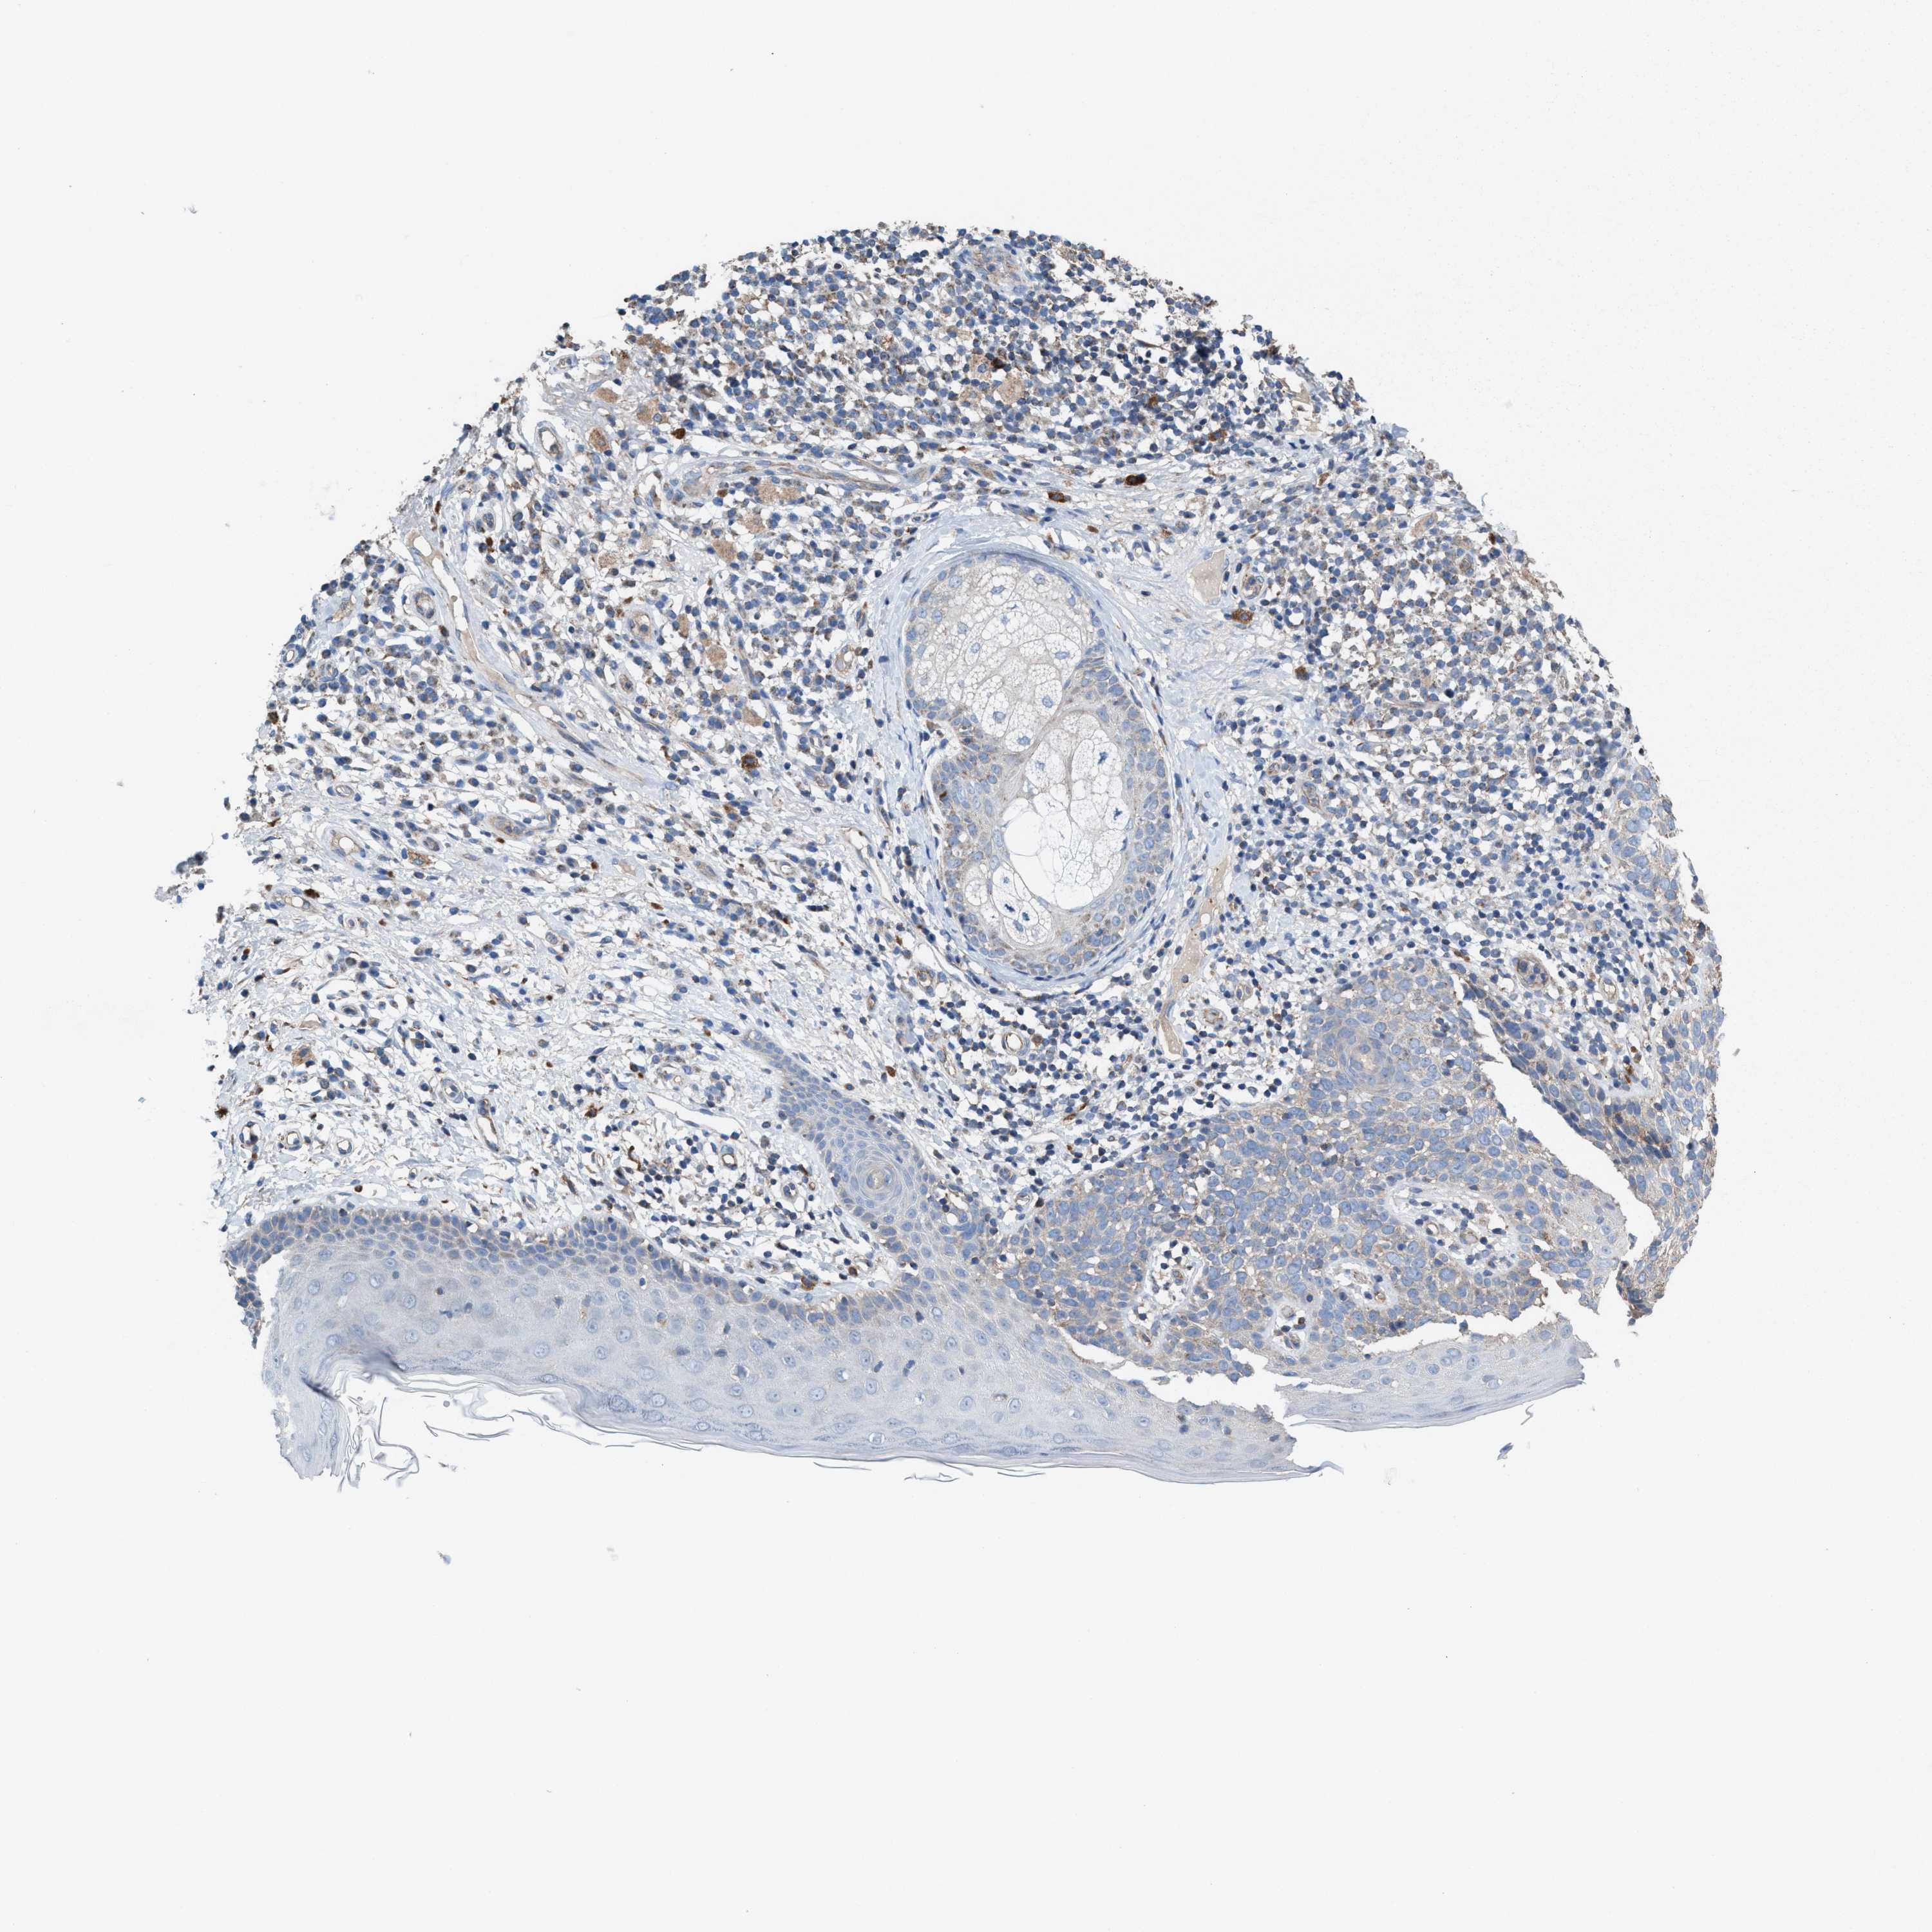

SKIN CANCER - Protein expressioni

A mouse-over function shows sample information and annotation data. Click on an image to view it in a full screen mode. Samples can be filtered based on level of antibody staining by selecting one or several of the following categories: high, medium, low and not detected. The assay and annotation is described here.

Each image is clickable and will lead to virtual microscopy that enables deeper exploration of all samples and also displays staining intensity scores, fraction scores and subcellular localization as well as patient and tissue information for each sample.

Antibody HPA021598

Squamous cell carcinoma in situ, NOS

Squamous cell carcinoma, NOS

Squamous cell carcinoma, metastatic, NOS

Basal cell carcinoma

Adnexal tumor, benign